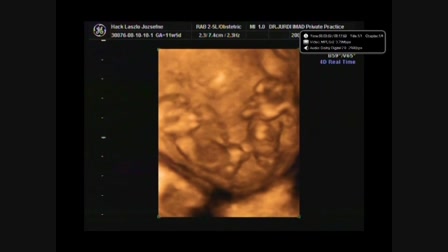

Tomyboy XXX (szülinapra) :)

Kreáltam az öcsémről egy kisvideót a harmadik X-e alkalmából! :) Ez az első próbálkozásom, de intenzíven tanulok! :)